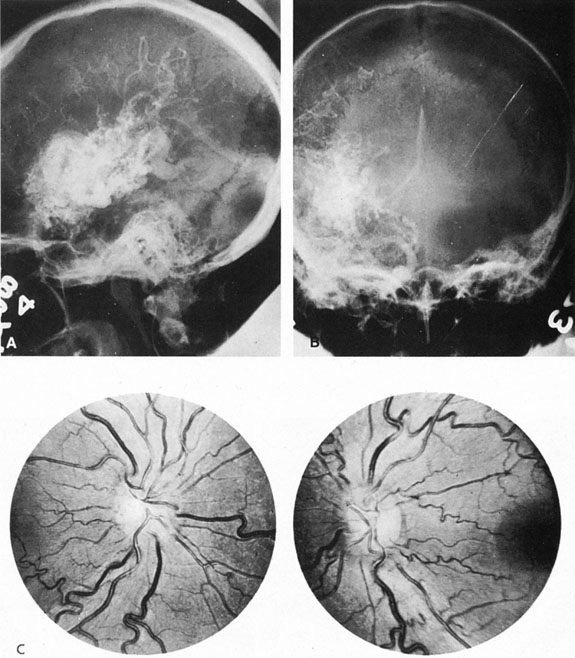

The detection of intracranial AVMs is facilitated by CT scanning and MRI (Fig. 10),88 but optimal management requires selective angiography89 that assesses the size and configuration of the mass, the number and location of feeding arteries, the flow characteristics and degree of steal from brain parenchyma, and the pattern of venous drainage.

Fig. 10. Neuroimaging of arteriovenous malformation. A: Coronal magnetic resonance imaging (MRI) (TR, 600 ms; TE, 20 ms) shows wedge-shaped vascular mass extending from the surface of the parietal cortex (white arrows) to the lateral ventricle (black arrows; asterisk, arterial feeder). B: Posteroanterior left arteriogram of the same lesion. C: Axial computed tomography scan with contrast enhancement. D: Axial MRI of a large arteriovenous malformation, first echo (TR, 2000 ms; TE, 20 ms). E: Second echo (TR, 2000 ms; TE, 90 ms). (From Smith HJ, Strother CM, Kikuchi Y, et al: MR imaging in the management of supratentorial intracranial AVMS. AJNR Am J Neuroradiol 9:225, 1988.)